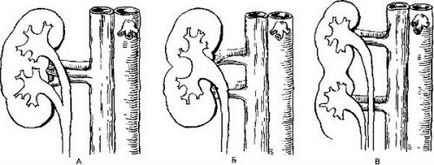

Сплит - състояние, характеризиращо се с пълна или непълна система разделяне pyelocaliceal (CHLS) на тялото на две части. Най-често това се отразява на около един в бъбрека, но може да повлияе и на двете тела CHLS двойка.

За да видите как изглежда разделен на бъбреците, и да разберат какво е да се проведе просто диагноза е достатъчно, например, ултразвукови: на засегнатия бъбрек прилича на два слети и всяка от които има на бъбречната артерия.

Раздвоения бъбрек се увеличи значително. Ако непълно разделяне CHLS цяло остава в пълна - се трансформира в две независими системи с индивидуални уретери - основна и разширение. В последната може самостоятелно растат в кухината на пикочния мехур или свързване с основната преди да влезе в балона. Ако двата уретера се сливат, на мястото на тяхната връзка се образува стеснение, че може да прекъсне потока на процеса на урина и обратната му актьорски състав в таза. Такава протичане на заболяването може да бъде най-хидронефроза - разширение чаши и таза - и последваща атрофия на бъбречната паренхим.

Има няколко анатомични варианти удвояване на бъбреците